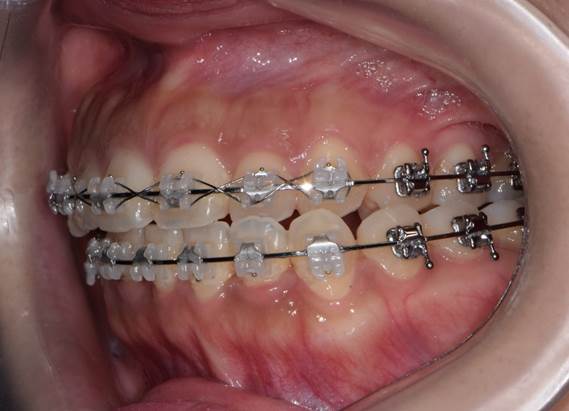

구내 우측모.jpg

구내 정모.jpg

구내 좌측모.jpg

위턱 치아의 중심선에 비해 아래턱 치아의 중심선이 좌측으로 돌아가 있다.

위 환자는 안면 비대칭이 있는 환자로, 처음 병원에 내원한 후 수술 전 교정이 필요하다고 진단을 받고, 1년 가까이 교정을 받고 수술을 위해 다시 내원한 환자입니다.